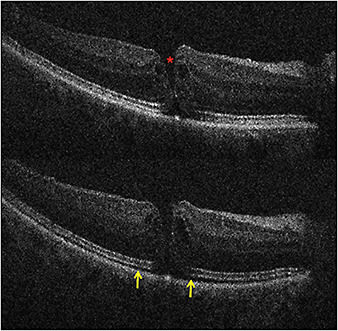

Figure 2. Top) Preincision iOCT B-scan revealing full-thickness macular hole (red asterisk). Bottom) Postpeel iOCT B-scan revealing expansion of the subretinal hyporeflectivity band between the photoreceptor layers and the retinal pigment epithelium (yellow arrows).